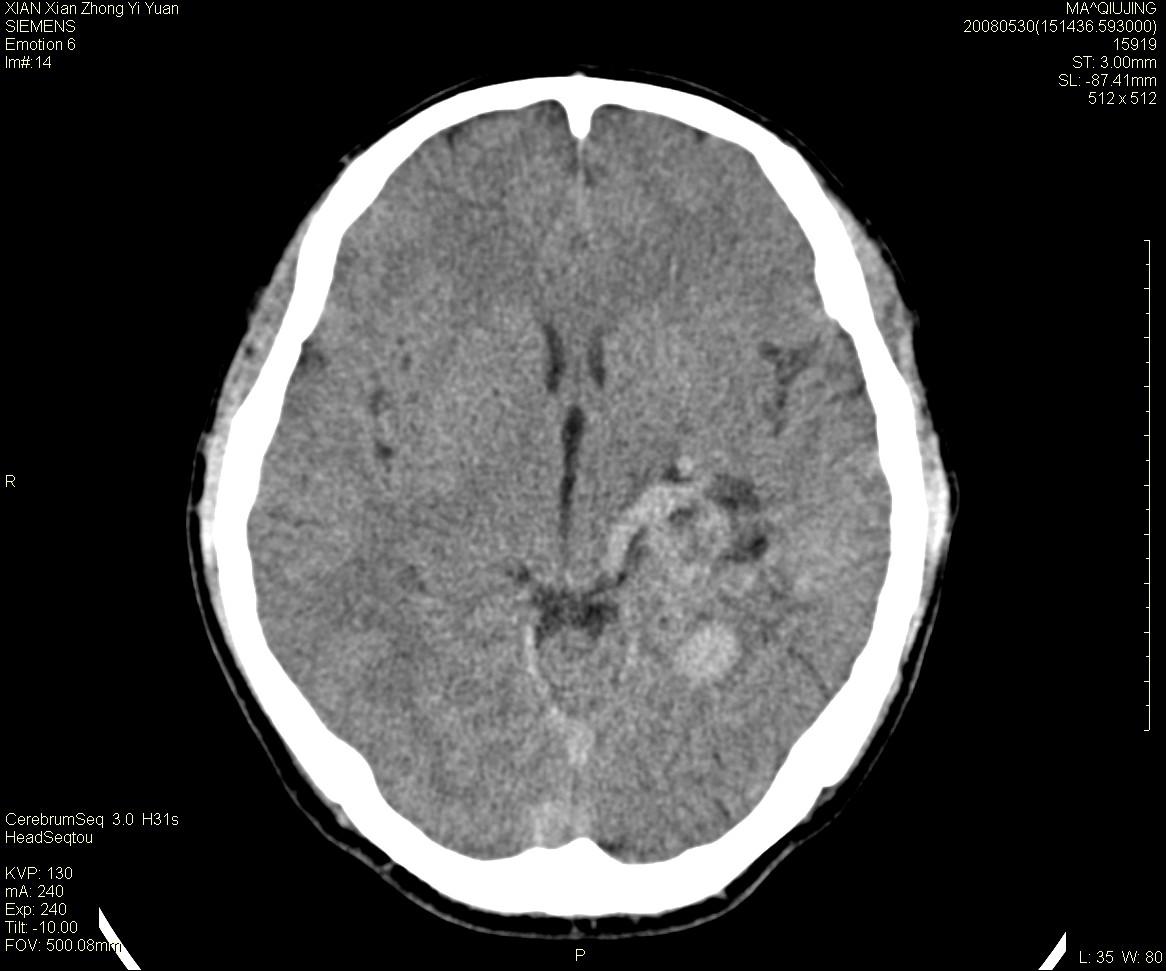

标题: CT13768:少见病例,血管畸形。

患者m47,头晕数年,没给强化,让做dsa去了。

avm

第一感觉:avm,但其中更低密度区不清楚,好像有脂肪密度,胆脂瘤破裂?

avm,低密度区应该是以前出血过的液化灶

血管畸形,支持,如果增强扫描,则可见粗大,迂曲血管团。